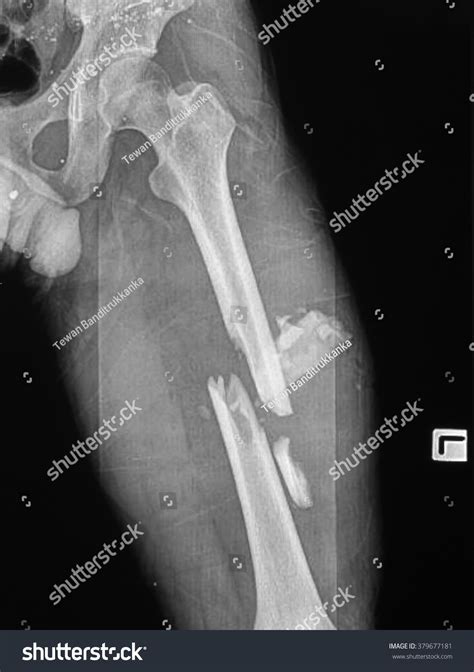

A broken femur recovery is widely considered one of the most physically and mentally demanding orthopedic journeys a patient can undergo. As the largest and strongest bone in the human body, the femur requires significant force to break, usually resulting from high-impact trauma such as motor vehicle accidents or severe falls. Because the bone is so substantial, the healing process is complex, involving intricate surgical repairs, long periods of immobilization, and a rigorous rehabilitation schedule. Understanding the stages of this recovery process is essential for setting realistic expectations and ensuring long-term mobility.

Following the surgical repair—typically involving intramedullary nailing, plates, or screws—the first few weeks are focused on stabilization and pain management. During this time, the body initiates the "inflammatory phase" of healing, where blood clots form and the body begins to clear away damaged tissue. It is critical to follow the surgeon’s weight-bearing restrictions strictly, as putting pressure on the leg too soon can displace hardware or interfere with bone union.